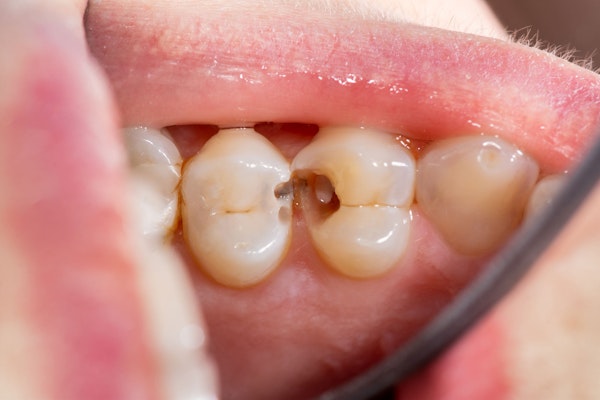

Seeking dental care in a timely manner can prevent the need for procedures like extractions, implants, and crowns. Don't know what to look out for? If you're experiencing these symptoms, contact the team at our dental office in Warsaw, IN, immediately:

Newly-Darkened Enamel

With timely intervention, we may be able to avoid the need for an extraction altogether. We'll only choose that treatment option if we can't save your tooth.